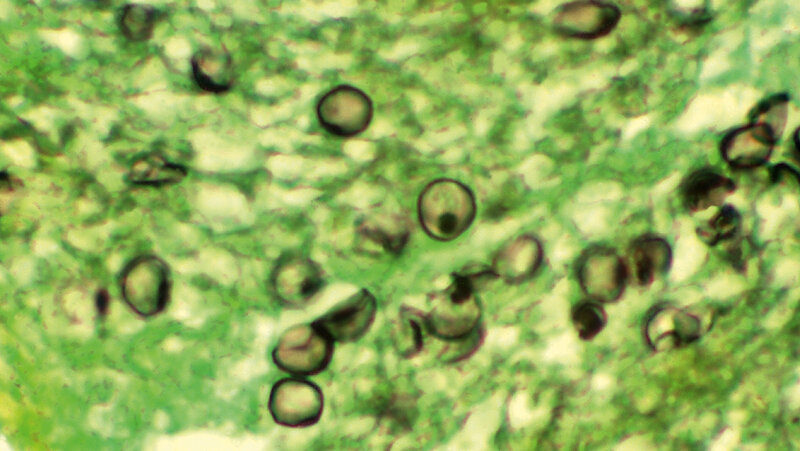

Zur Behandlung von systemischen Pilzinfektionen stehen nur wenige Substanzklassen zur Verfügung, nämlich Polyene, Azole und Echinocandine. Die Polyene attackieren Ergosterol in der zytoplasmatischen Membran der Pilze; die Azole hemmen die Bildung von Ergosterol; die Echinocandine unterbinden die Synthese von 1,3-β-Glucan in der Zellwand der Pilze. Primäre Resistenzen kommen bei einigen Pilzen vor. Pneumocystis zum Beispiel ist resistent gegen Amphotericin B und gegen Azole, weil die kein Ergosterol ausbilden. Auch sekundäre Resistenz unter dem Einfluss von Antimykotika kann entstehen. Entweder weil der Zugang des Antimykotikums ans Target unterbunden wird. Effluxpumpen spielen dabei eine Rolle. Oder das Target ist mutiert und der Wirkstoff kann nicht binden und seine Aufgabe erfüllen. Eine Bildung von Enzymen, welche die Antimykotika zerstören, gibt es nicht! Auch die vertikale Verbreitung von Resistenzeigenschaften durch mobile genetische Elemente, wie Transposons und Plasmide, findet nicht statt. Eine explosionsartige Ausbreitung von Resistenzen beobachtet man bei Pilzen also weitaus seltener. Eine horizontale Ausbreitung, wobei die Resistenz während der Vermehrung auf die Nachkommenschaft vererbt wird, ist auch bei Pilzen möglich.

There are only few classes of drugs available for the therapy of systemic fungal infections, namely polyenes, azoles and echinocandins. Polyens attack ergosterol in the cytoplasmic membrane of fungi; azoles inhibit the formation of ergosterol; echinocandins interfere with the production of (1,3)-β glucan in the cell wall. Primary resistance occurs in a few fungi, for example in Pneumocystis, which does not yield ergosterol. Secondary resistance may also develop under the influence of antimycotics. The access of antimicrobials to their target is blocked for example by means of efflux pumps. Or, the target has undergone mutations, so that the agent is no longer able to bind and exert his function. But the formation of enzymes destroying the antimycotics has not yet been found in fungi. In addition, the vertical spreading of resistance properties by mobile genetic elements such as transposons and plasmids are unknown in fungi. Hence, explosive dissimination of resistant fungi is rare. Of course, horizontal spreading due to bequested transfer of resistance traits during multiplication occurs in fungi, too.